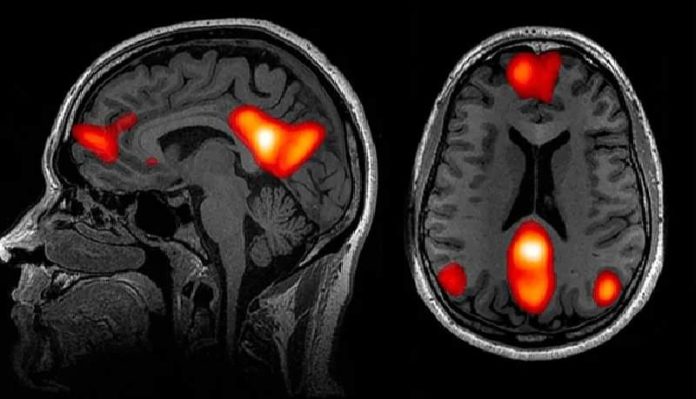

Njihova otkrića, objavljena 2020. u časopisu Nature Communications, otkrila su da žarište usamljenosti mozga vreba unutar zadane mreže, dijela mozga koji se aktivira kada smo u stanju mentalne pripravnosti. “Do prije 20 godina nismo ni znali da imamo ovaj sustav”, rekao je Bzdok. Međutim, studije su pokazale da aktivnost u zadanoj mreži čini većinu potrošnje energije mozga.

Bzdok i njegov tim pokazali su da su neke regije zadane mreže ne samo veće kod ljudi koji su kronično usamljeni, već su i jače povezane s drugim dijelovima mozga. Nadalje, čini se da je zadana mreža uključena u mnoge osebujne sposobnosti koje su se razvile kod ljudi, kao što su jezik, predviđanje budućnosti i uzročno zaključivanje. Općenitije, zadana mreža se aktivira kada razmišljamo o drugim ljudima, čak i kada tumačimo njihove namjere.

Nalazi o zadanoj mrežnoj povezivosti pružili su dokaz neuroimaginga koji podupire prethodne nalaze psihologa da usamljeni ljudi imaju tendenciju sanjariti o društvenim interakcijama, lako postaju nostalgični u vezi prošlih društvenih događaja, pa čak i antropomorfiziraju svoje ljubimce, razgovarajući sa svojim mačkama kao da su ljudi, jer primjer. “Za to bi također bila potrebna zadana mreža”, rekao je Bzdok.